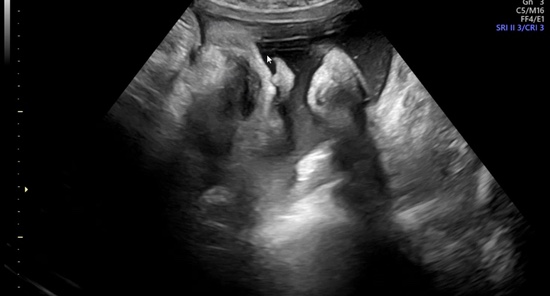

[임신 기록] 36주차 ~ 39주차 기록 | 뽀룡이 역아 탈출! | 마지막 주수 사진 남기기 | 이케아 수유등 구매 | 호르몬의 노예 | 출산 가방 챙기기 | 유도분만 날짜 잡기

나의 마지막 임신 기록 ^ㅁ^ 벌써 임신 10개월차! 이걸 올리는 지금은 병원에 입원 중! 순산하게 해주세요,...